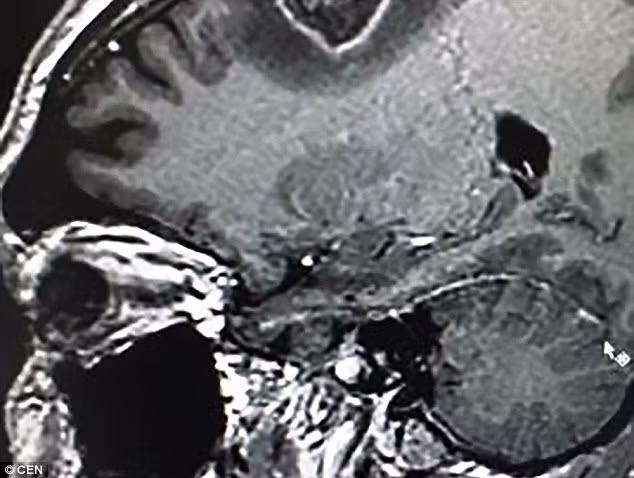

Bệnh nhân Rolden Batista, 40 tuổi, được các bác sĩ đưa cho một cây đàn guitar vào giữa ca mổ phức tạp để loại bỏ khối u hình trái tim trong đầu. Trước sự ngạc nhiên của các bác sĩ, bệnh nhân này đã vừa đàn vừa hát một bài hát truyền thống của Brazil.

Vào năm ngoái, anh Rolden từng vài lần gây rắc rối vì lên cơn, đây là một tín hiệu cảnh báo cho thấy có gì đó không ổn. Khi đến kiểm tra tại một bệnh viện địa phương, kỹ sư thông tin này mới biết mình có một khối u trong não hình trái tim và phải phẫu thuật.